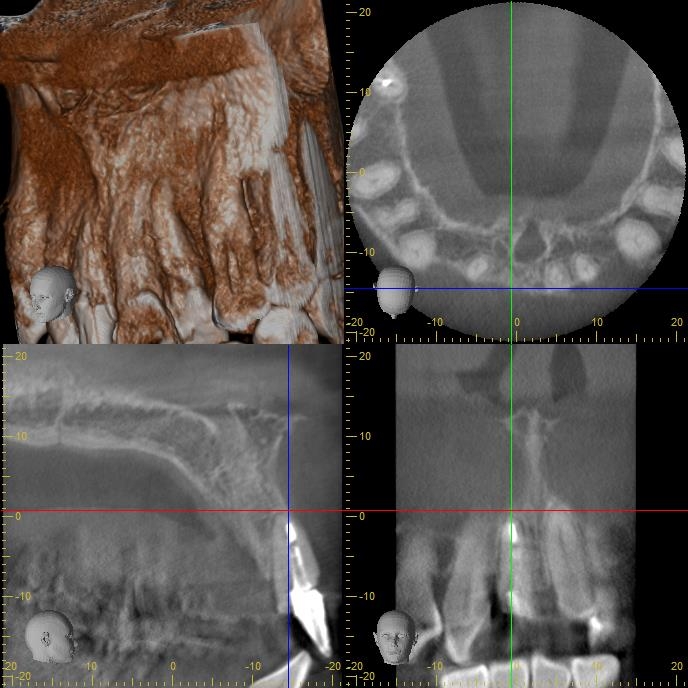

CT撮影 (術前)